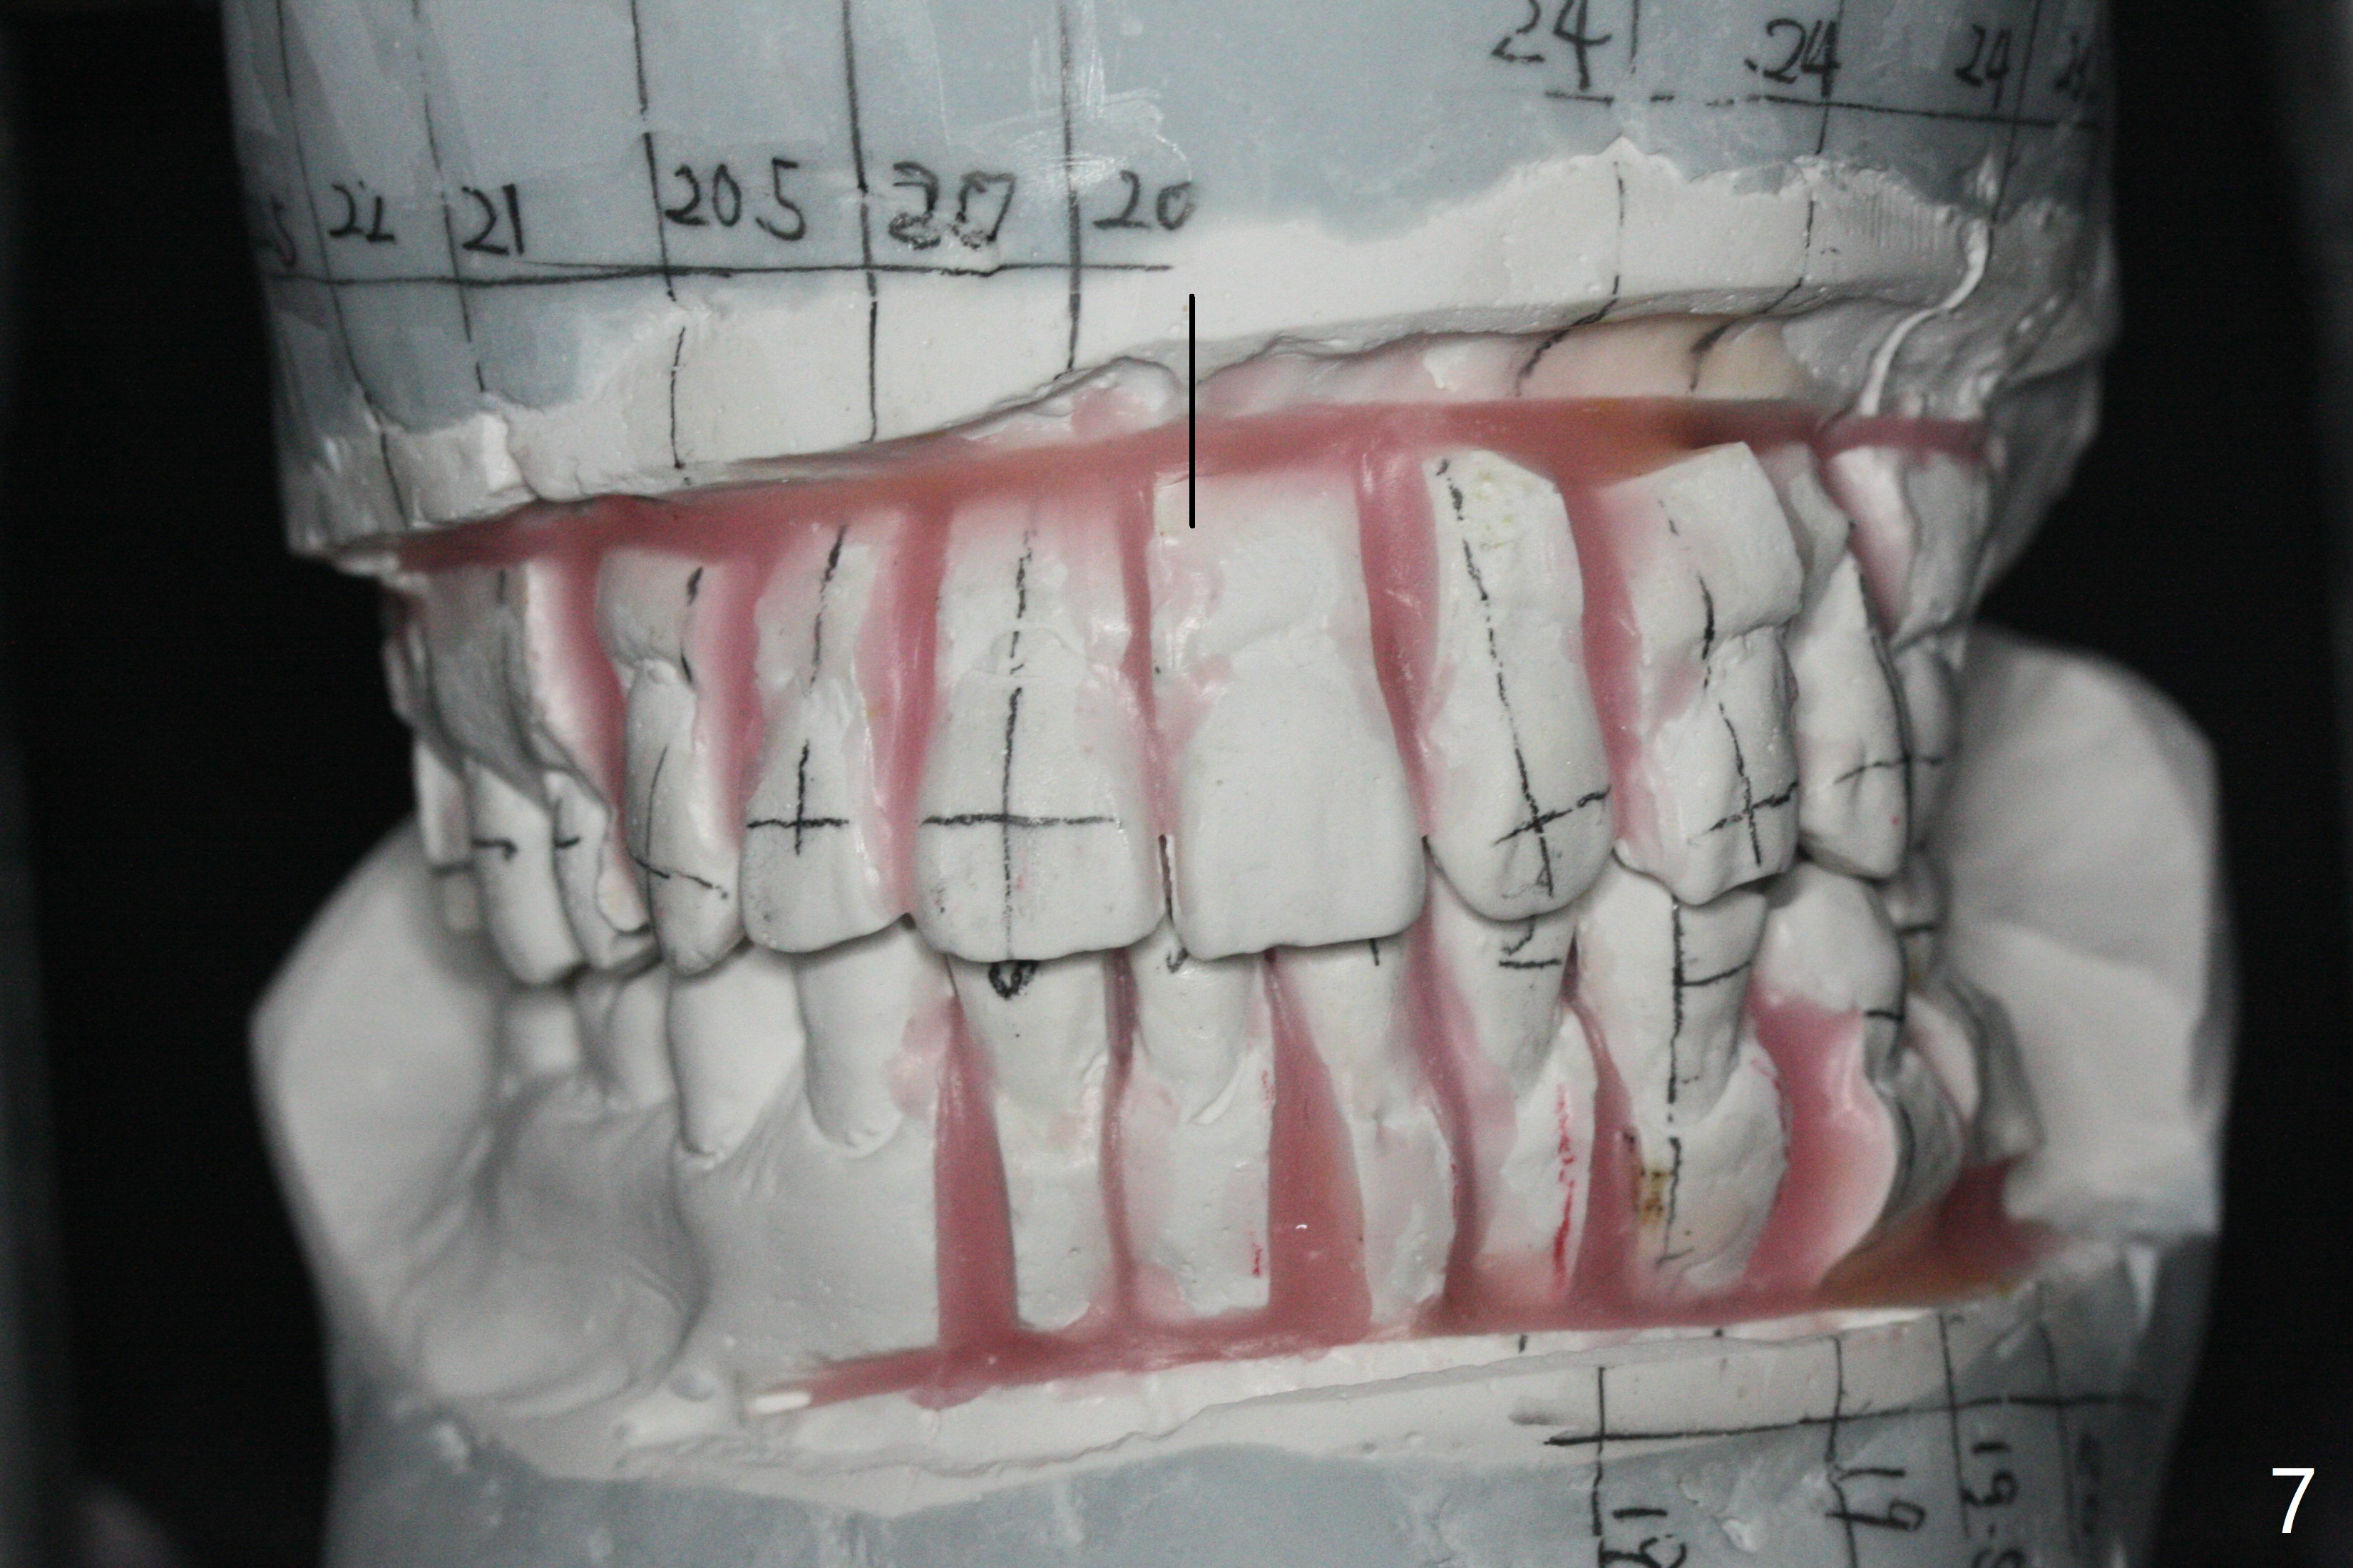

A 54-year-old man remains difficult in mastication in spite of implant placement at #14 and 31 (Fig. A, B, E, including screw loosening (poor trajectory at #14)). In addition to 2 more implants at #15 and 18 with guide, malocclusion seems to be necessary to be addressed (Fig.1-5). It appears that UR, LL4 should be extracted for orthodontic treatment (Fig.6-10). To reduce screw loosening, IS guide will be used to place IBS (5x9mm) and tissue-level (5x11mm) implants at #15 (PRF)and 18, respectively. If the one at #14 or 15 keeps loosening, splint #14 and 15 crowns. In fact the patient agrees with limited ortho (UR7 cross bite).